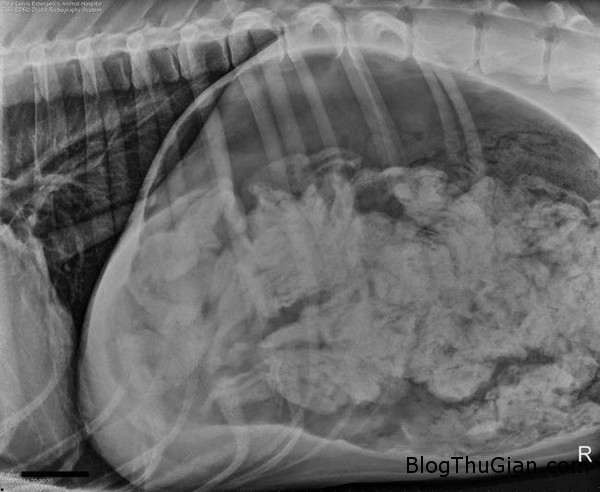

Hình chụp X-quang dạ dày của chú chó.

Kết quả chụp X-quang cho thấy, trong dạ dày của chú chó Great Dane có một số lượng dị vật. Các bác sĩ nghi ngờ chú chó này đã ăn tất của chủ nhân khi đói miệng. Phải mất tới hơn 2 tiếng đồng hồ phẫu thuật, họ mới gắp bỏ được tổng cộng 43 chiếc tất ra khỏi dạ dày của con vật. Ngoài ra, các bác sĩ còn tìm thấy 1 vật có hình dáng như gót giày cũng bị nó nuốt phải.